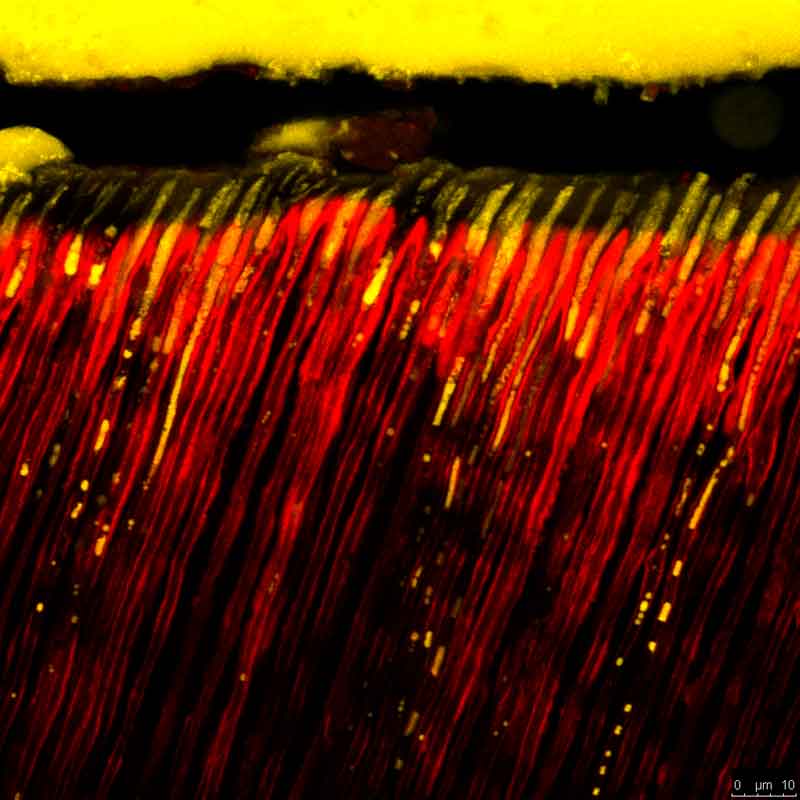

Ig6